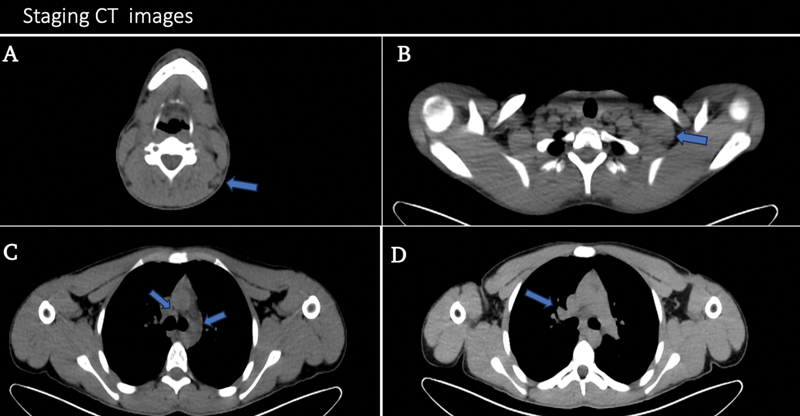

肉样瘤病经常与各种血液肿瘤和实体瘤相关;它可能在肿瘤评估时偶然被发现。肉样瘤病可能发生在某些癌症之前,也可能与其他癌症并存,或在 1 到 2 年后才被诊断出来。对于组织病理学确诊为霍奇金淋巴瘤并正在接受氟脱氧葡萄糖-正电子发射计算机断层扫描(FDG-PET/CT)评估的患者来说,影响肺门淋巴结和纵隔淋巴结的肉样瘤反应会给诊断带来挑战,因为肉样瘤反应不易与淋巴瘤浸润区分开来。如果淋巴瘤化疗后的随访 FDG-PET/CT 扫描中出现明显的活动性增加或持续存在,且与主要确诊淋巴瘤疾病部位的完全代谢反应相关联,则高度提示并发肉样瘤病,有必要进行仔细评估,以避免不必要的治疗。

Sarcoidosis is frequently associated with various hematological and solid tumors; it can be discovered by chance during tumor evaluations. Sarcoidosis can occur before some cancers, coexist with others, or be diagnosed 1 to 2 years later. Sarcoid reaction affecting hilar and mediastinal lymph nodes can pose a diagnostic challenge in patients with histopathological confirmation of Hodgkin lymphoma who are being evaluated using fluorodeoxyglucose-positron emission tomography computed tomography (FDG-PET/CT) scan because it cannot be easily distinguished from lymphoma infiltration. The presence of an increase or persistence of a prominent activity on a follow-up FDG-PET/CT scan after chemotherapy treatment for lymphoma that is associated with a complete metabolic response in the site of the primarily diagnosed lymphomatous disease is highly suggestive of concurrent sarcoidosis and necessitates careful assessment to avoid unnecessary therapy.